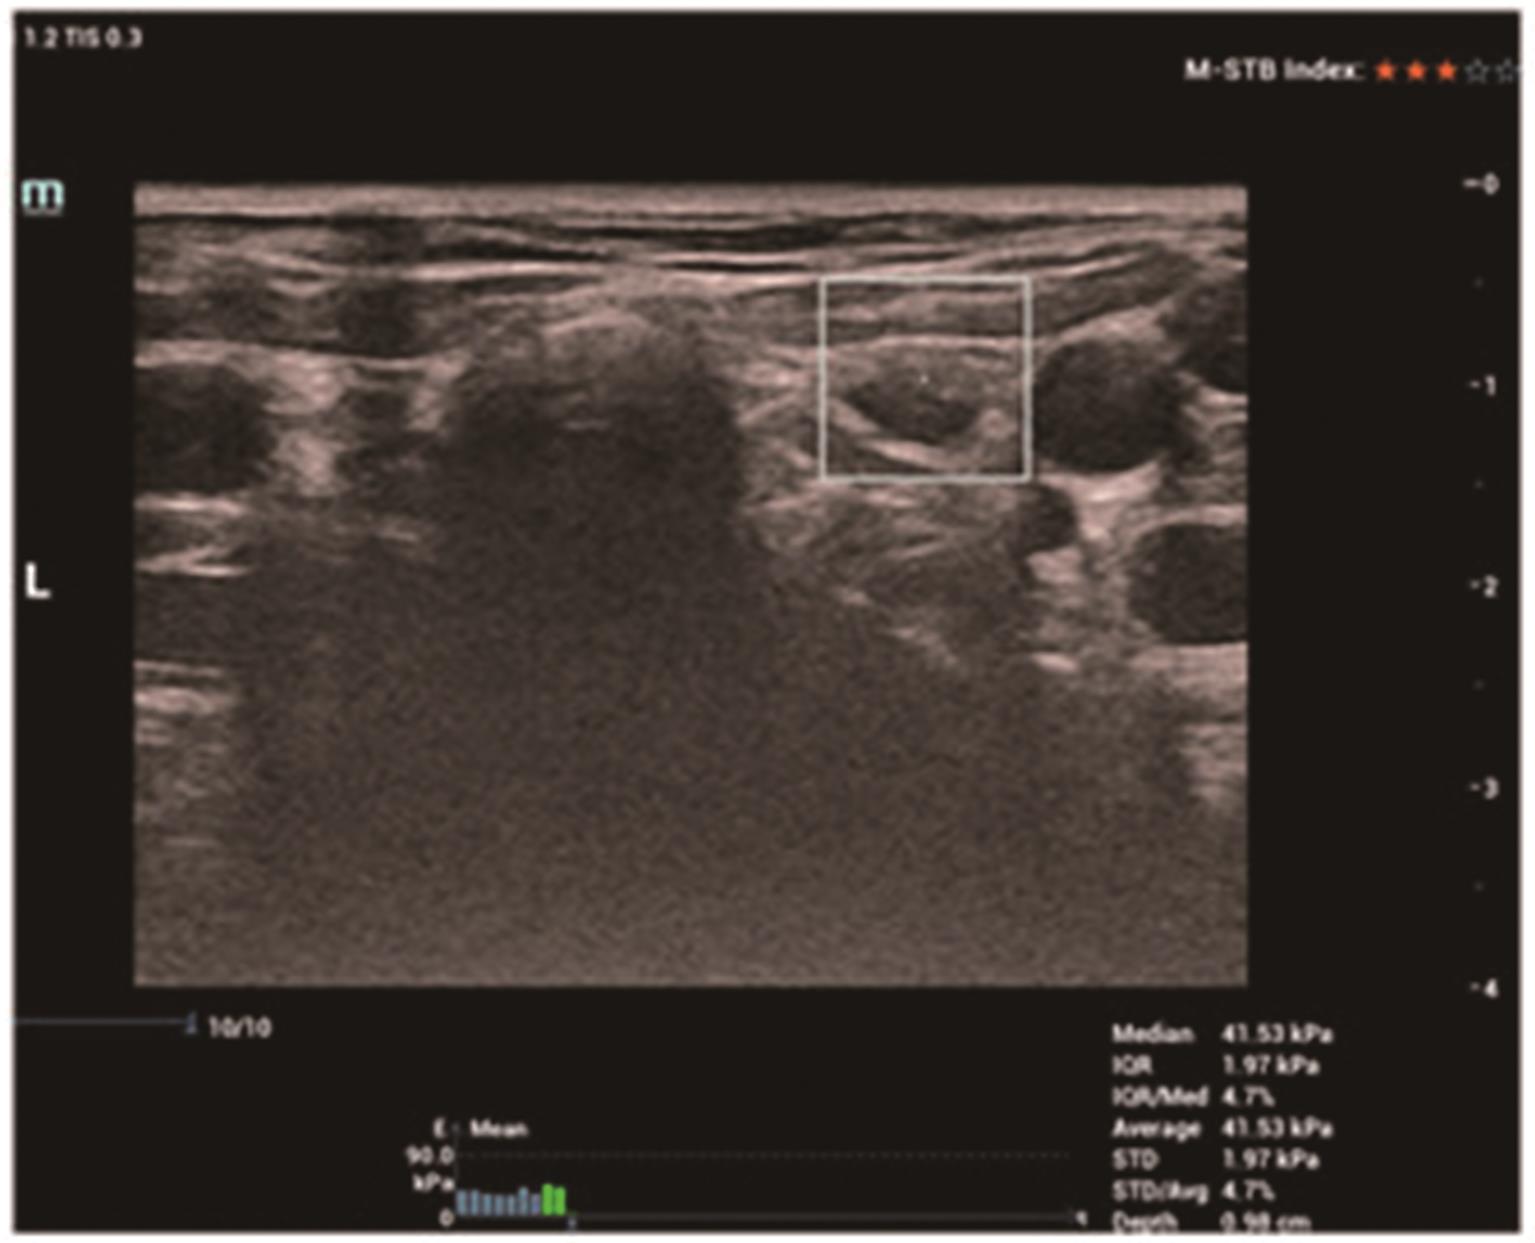

• 剪切波弹性成像与FNA-Tg对甲状腺乳头状癌侧颈部淋巴结转移的诊断价值

2023, 48(4):462-466. DOI: 10.13406/j.cnki.cyxb.003206

摘要 (105) HTML (21) PDF 1.03 M (225) 评论 (0) 收藏

摘要:目的 探讨剪切波弹性成像(shear wave elastography,SWE)与细针穿刺洗脱液甲状腺球蛋白(fine-needle aspiration washout thyroglobulin,FNA-Tg)对甲状腺乳头状癌侧颈部淋巴结转移的诊断价值。方法 回顾性分析159例经病理证实为甲状腺乳头状癌(papillary thyroid carcinoma,PTC)的患者资料,对颈部211枚可疑淋巴结进行常规超声、SWE参数平均值(Emean)、FNA-Tg检查,以术后病理结果为金标准,比较各检测方法的诊断效能。结果 ①SWE Emean转移组[(50.96±27.66) kPa]高于非转移组[(32.20±17.34) kPa],差异有统计学意义(t=8.761,P<0.01)。受试者工作特征(receiver operating characteristic,ROC)曲线分析表明,SWE Emean最佳诊断阈值为40.42 kPa时对PTC颈部淋巴结转移预测价值较高,曲线下面积(area under the curve,AUC)为0.849(95%CI=0.795~0.902,P<0.01)。②与SWE Emean比较,联合法敏感度、特异度、准确度、阳性预测值及阴性预测值均显著提高(χ2=7.724、28.230、35.094、21.731、9.890,P=0.005、<0.000、<0.000、<0.000、0.002)。与FNA-Tg比较,联合法敏感度、特异度、准确度、阳性预测值及阴性预测值也显著提高(χ2=7.724、6.014、13.526、6.137、7.602,P=0.005、0.014、<0.000、0.013、0.006)。③在淋巴结有囊性变和无囊性变时,SWE Emean的准确度分别为53.8%和79.8%,差异有统计学意义(χ2=4.819,P=0.028);FNA-Tg的准确度分别为92.3%和87.4%,差异无统计学意义(χ2=0.275,P=0.600)。结论 FNA-Tg诊断PTC转移淋巴结的准确度较高,且不受淋巴结有无囊性变的影响,与SWE Emean联合后可显著提高诊断效能。

• 0+1

• 1+1

• 2+1

• 3+1